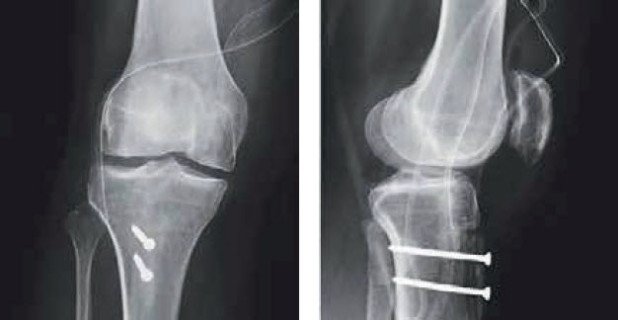

Eine junge Patientin erlitt bei einem Sportunfall eine Luxation der Patella, wobei ein grosses Knorpel-Knochen-Stück aus der Patellarückfläche abgesprengt wurde und das MPFL riss. Ferner wies die Patientin seit der Geburt eine zu weit nach aussen orientierte Zugrichtung der Kniescheibensehne auf. Im Rahmen eines gezielten Eingriffs wurde bei der Patientin initial das grosse Knorpel-Knochen-Stück unter Verwendung von sich auflösenden Zuckerschrauben wieder an der Kniescheibe befestigt. Im nächsten Schritt der Operation die Zugrichtung der Kniescheibensehne durch Neuorientierung des Ansatzes der Sehne nach innen und unten korrigiert. (Abb. 1 – 2, Normalisierung der Zugorientierung durch Versatz des Knochens-Tuberositastransfer- und folgende Schraubenbefestigung).